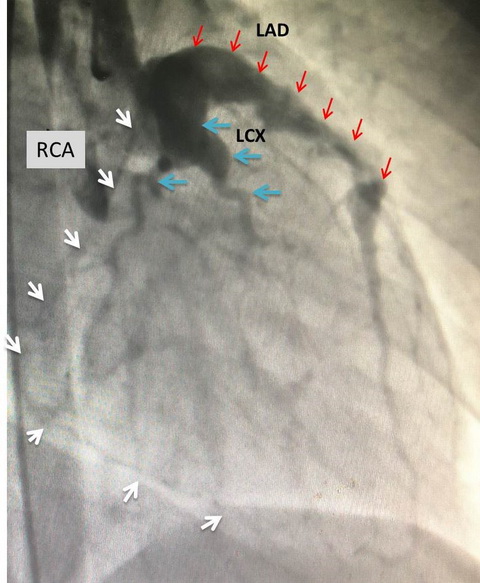

冠脉造影图。右冠(RCA,白色箭头)已完全闭塞,仅显示细小侧枝供应远端;左前降支(LAD,红色箭头)巨大瘤样扩张、血栓形成伴远端不规则狭窄;左回旋支(LCX,蓝色箭头):近端巨大瘤样扩张。